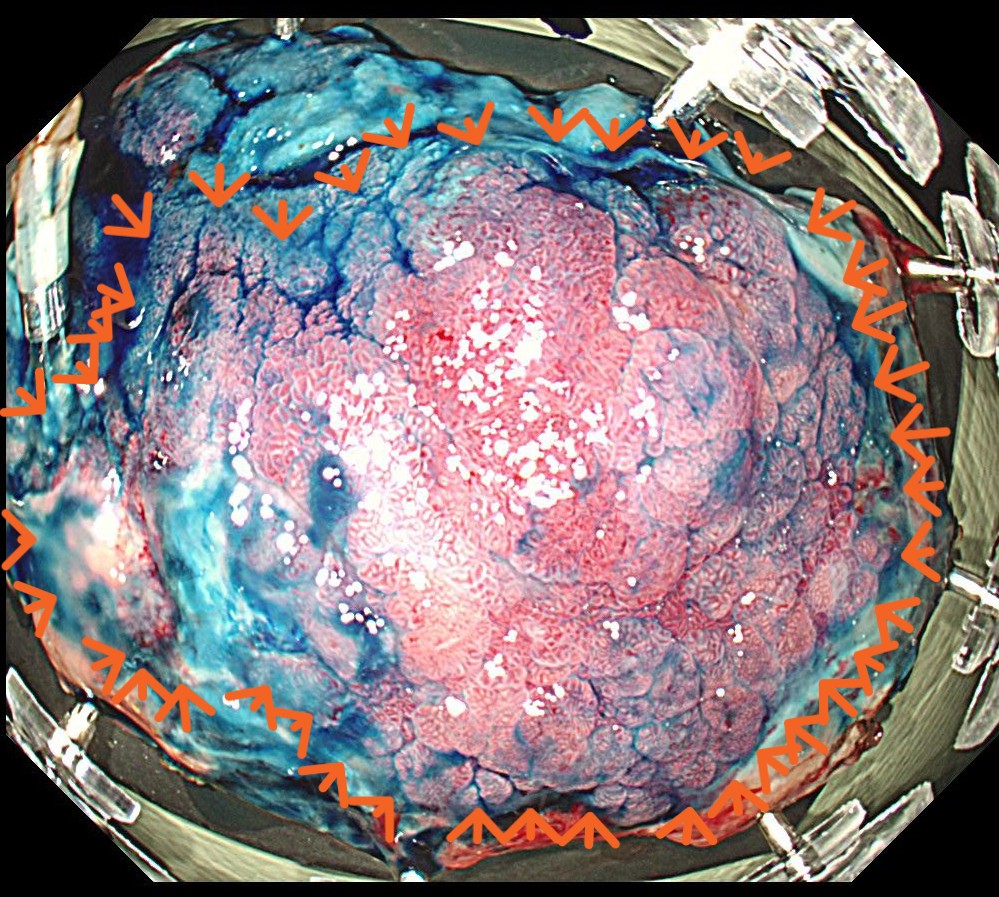

インジゴ散布で腫瘍の凹凸ははっきりします。

摘出標本です。高分化型粘膜内癌であり、根治切除と診断されました。